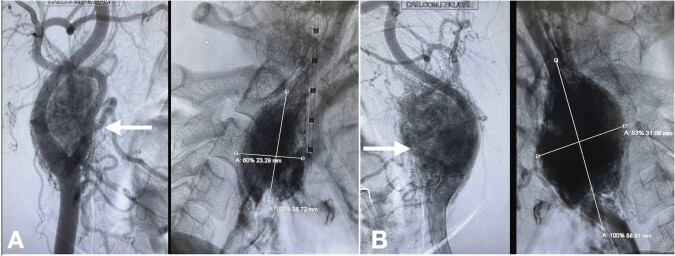

Bilateral paragangliomas are rare neuroendocrine tumors stemming from the paraganglia along the autonomic nervous system. This case report presents a case of a 49-year-old woman with a year history of bilateral neck masses and recurrent syncopal episodes. Diagnostic imaging revealed bilateral, hypervascular carotid body tumors. This case underlines the importance of recognizing paragangliomas as a differential diagnosis in patients with neck masses and highlights the role of advanced imaging techniques in diagnosis and management.